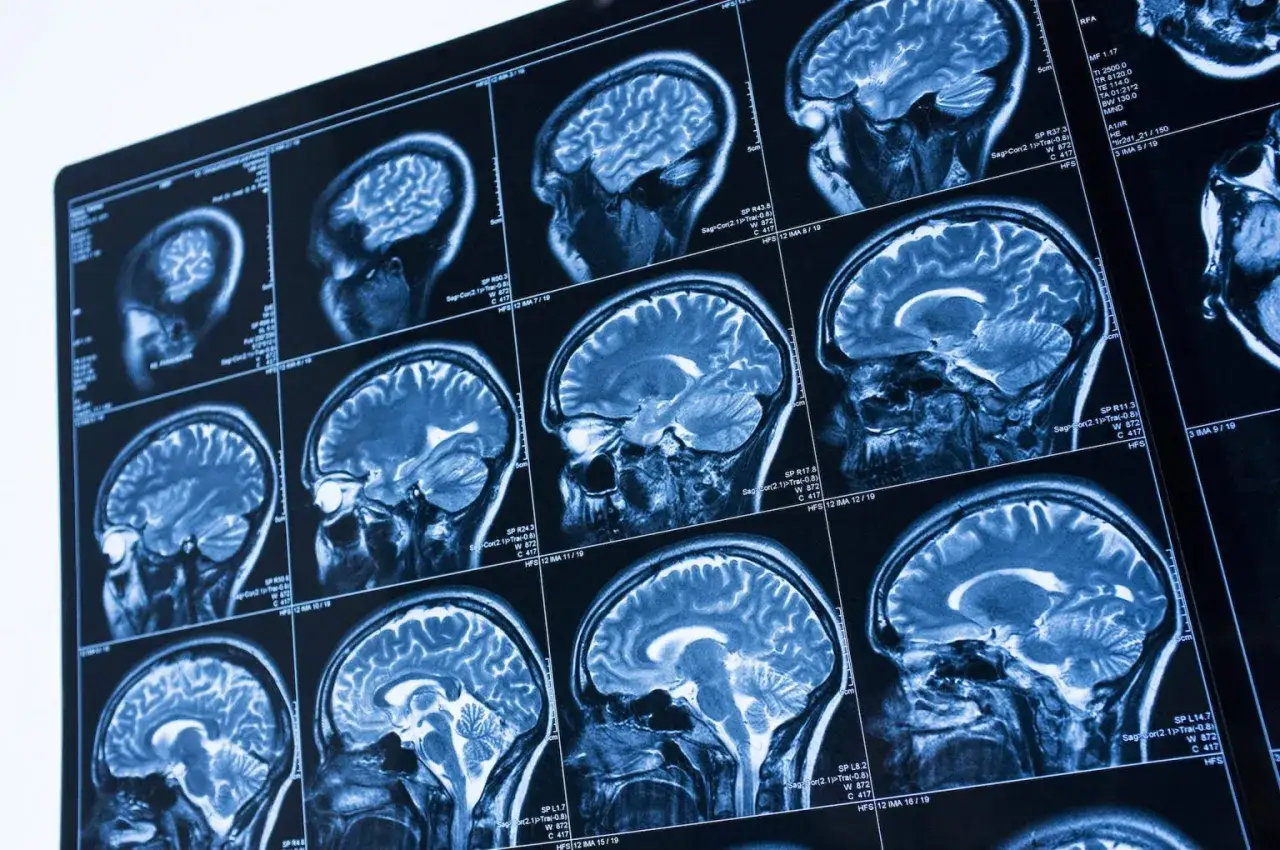

Rezonans magnetyczny (MRI) jest powszechnie uznawany za jedną z najbezpieczniejszych metod diagnostyki obrazowej. Dzieje się tak przede wszystkim dlatego, że w przeciwieństwie do tomografii komputerowej, badanie to nie wykorzystuje promieniowania jonizującego. Promieniowanie jonizujące, takie jak rentgenowskie, jest znane ze swojego potencjalnego negatywnego wpływu na organizm, dlatego jego brak w MRI jest kluczowym argumentem przemawiającym za bezpieczeństwem tej techniki. Mity dotyczące pola magnetycznego często budzą niepokój, jednak dla zdecydowanej większości pacjentów jest ono całkowicie bezpieczne. Aparat MRI generuje silne pole magnetyczne, ale nie ma ono udowodnionego negatywnego wpływu na tkanki żywego organizmu w sposób, w jaki robi to promieniowanie jonizujące. Dlatego właśnie MRI jest uważane za jedno z najbezpieczniejszych badań obrazowych dostępnych obecnie w medycynie.